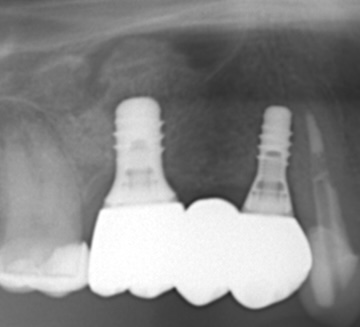

| 治療名 | サイナスリフトを併用したインプラントブリッジ症例 |

| 治療説明 |

奥歯に入っていたブリッジの支台歯にむし歯が見つかり、やむを得ず抜歯となりました。結果として奥歯が3本分欠損したため、患者さんとの相談のうえ、インプラントによる治療を選択しました。 |

| 治療回数・期間 | 約9ヶ月 |

| 副作用とリスク | ・入れ歯や従来のブリッジと比べ、治療期間が長くなる場合があります。 ・骨造成(GBRやサイナスリフト)を伴う場合、さらに治療期間が延びることがあります。 ・インプラント手術後には、一時的に違和感、痛み、腫れ、出血が生じることがありますが、通常は2日〜1週間で落ち着きます。 ・サイナスリフトは、まれに上顎洞への感染リスクがあるため、術後の経過観察が重要です。 |

| 料金(税込) | 小規模GBR:110,000円 サイナスリフト:220,000円 インプラント一次手術×2本:440,000円 二次手術×2本:110,000円 上部構造〈インプラントブリッジ〉:495,000円 合計:1,375,000円 |